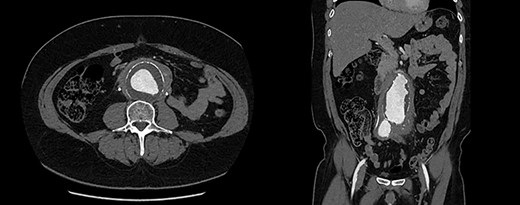

Blood tests demonstrated a severe AKI without significant neutrophilia but a mildly elevated C-reactive protein (Table 1). Given the flank tenderness and AKI, a non-contrast computed tomography of kidney, ureters and bladder (CT-KUB) was performed to exclude a renal or urological pathology. This demonstrated a large infra-renal AAA with surrounding retroperitoneal stranding and bilateral hydronephrosis (Fig. 1).

CT-KUB showing a large fusiform infra-renal AAA with moderate to severe retroperitoneal stranding (white arrow).